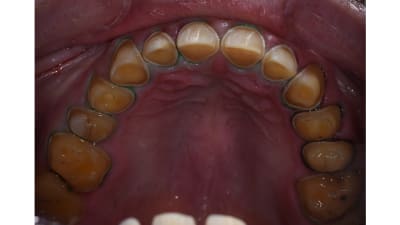

MasterClass Restorative Restorative Direct Diagnostically Driven Comprehensive Full-Mouth Rehabilitation By Dane Avondoglio, MS, DMD, Peter Pizzi, MDT, CDT In this case, consideration of the patient’s medical and dental history led to a diagnosis that explained the tooth wear and helped the patient’s sleep bruxism. June 01, 2025 13 min read